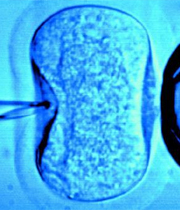

Jocelyn Edwards quiere someterse a un proceso de fecundación in vitro.

Una viuda australiana ganó este lunes la batalla legal por el esperma congelado de su difunto marido, aunque carece de la autorización escrita del donante requerida por la ley en el estado de Nueva Gales del Sur para someterse a la fecundación in vitro.

La decisión judicial concede a la viuda la potestad sobre los espermatozoides de su esposo, pero tendrá que buscar un lugar fuera de Nueva Gales del Sur para someterse a la fertilización in vitro.